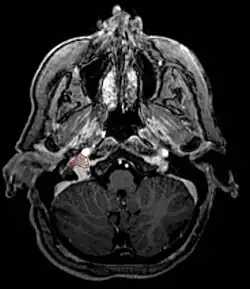

Glomus Jugulare

- Commonly arise from the paraganglia of the jugular bulb

- Typically invade the tympanic cavity and jugular foramen

- Can extensively invade petroclival region

- Can invade cavernous sinus above

- Can invade hypoglossal canal below

- Clinical presentation typically with tinnitus or hearing loss, but may also impact jugular foramen CNs